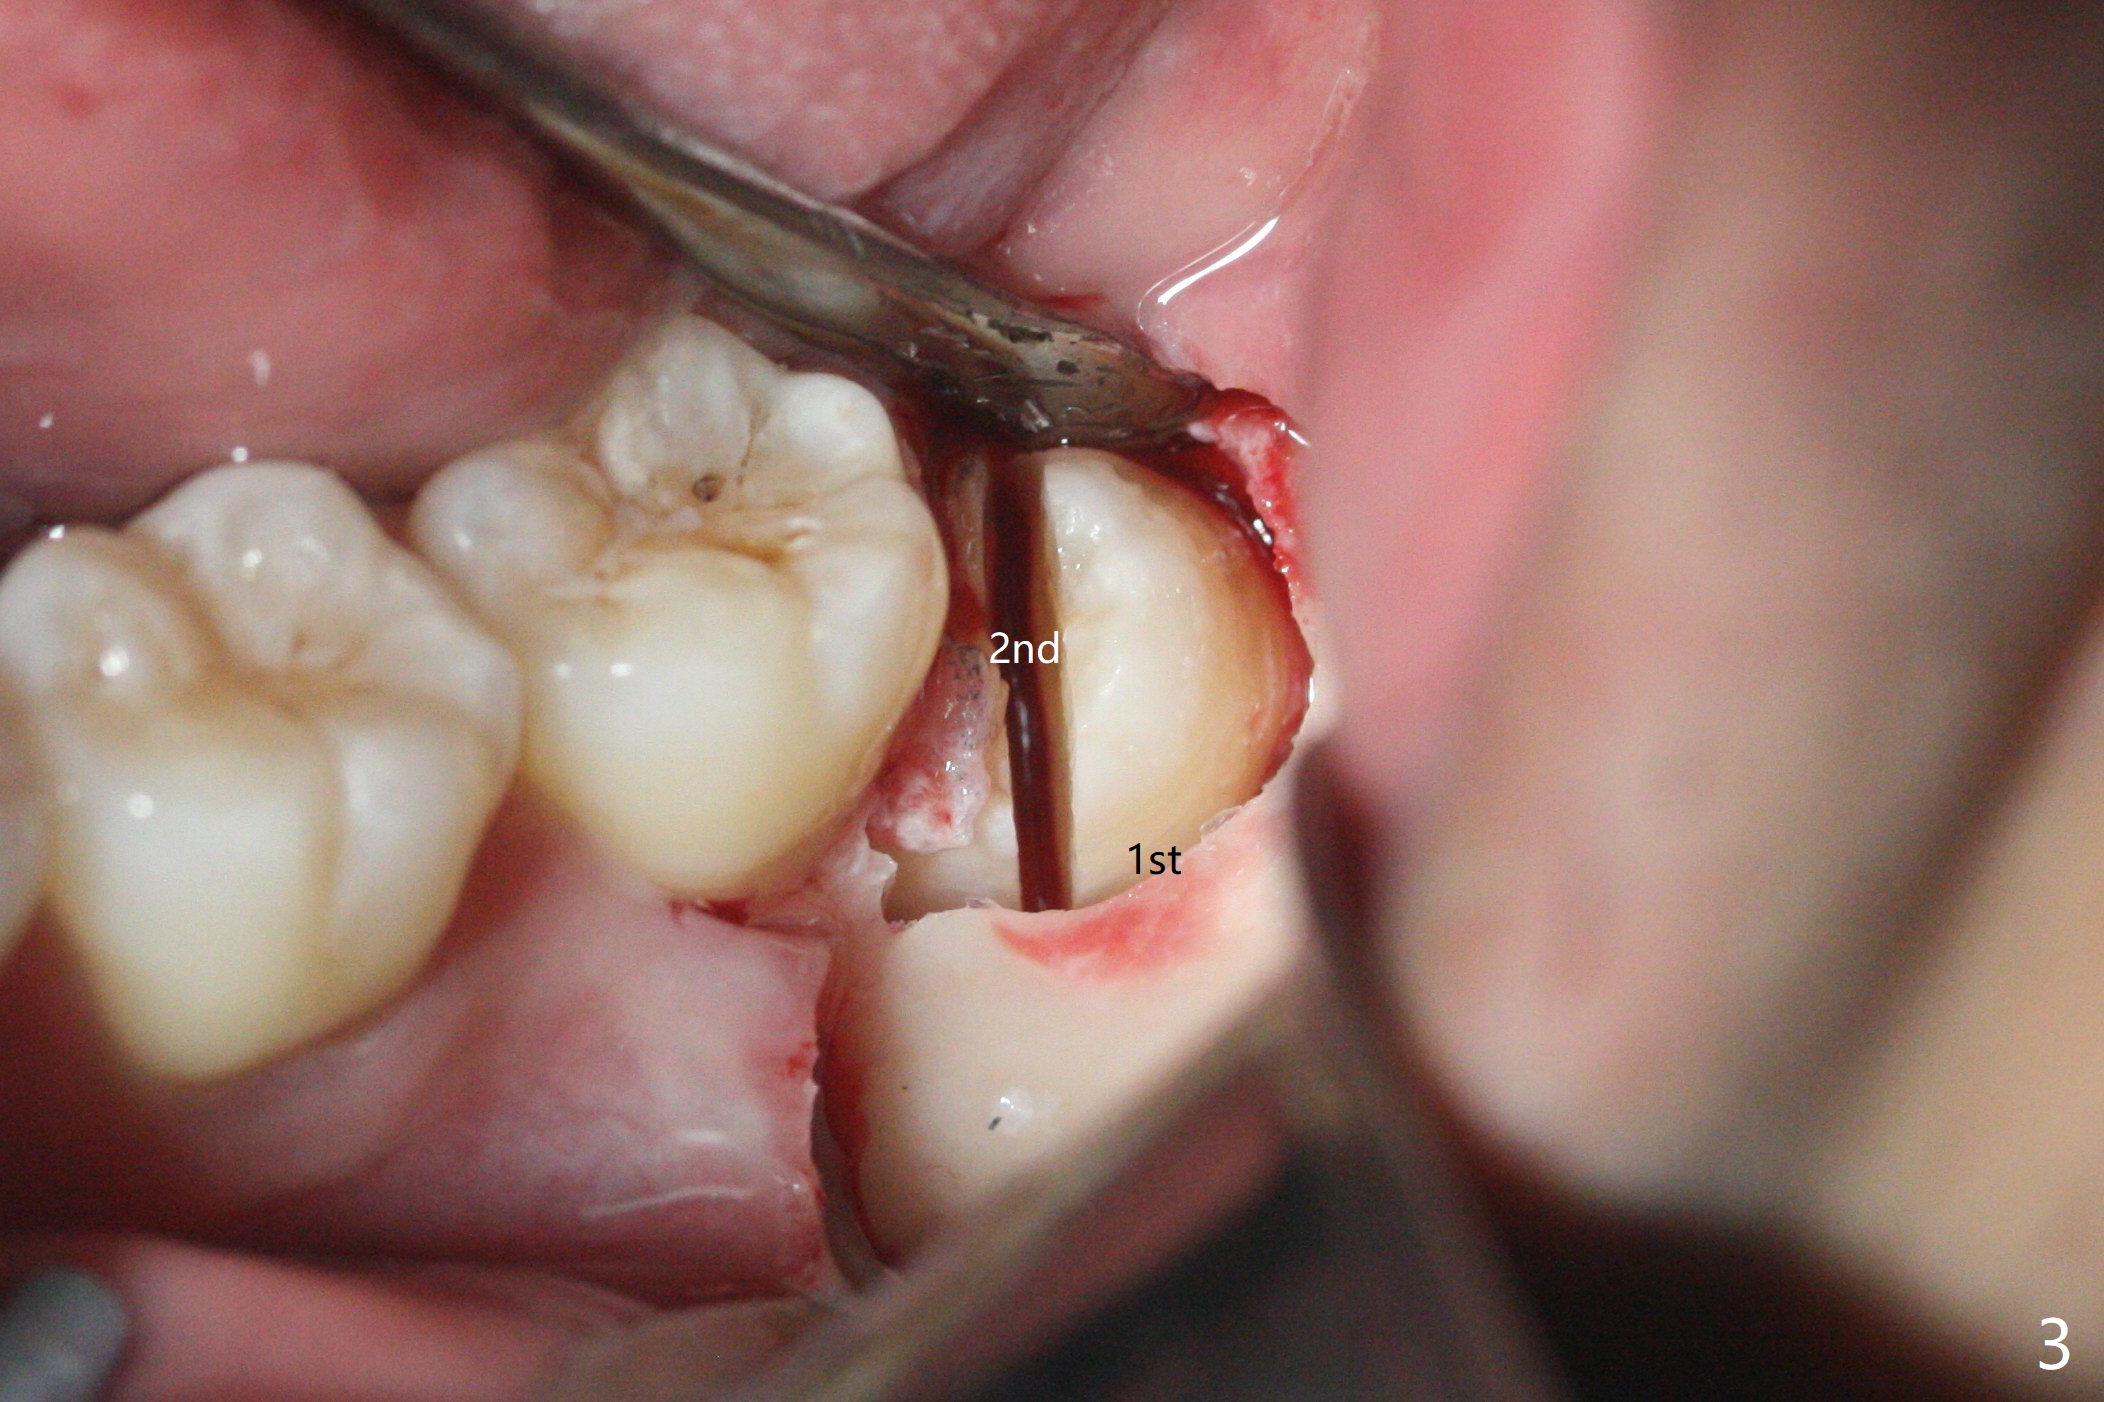

切口偏近中(图三),首先在智齿近中,颊侧,远中用外科裂钻形成沟(图三:1st),插入牙挺,在保护第二磨牙前提下,挺松智齿。如果患者骨质不硬,牙挺插入处骨质形成凹陷。然后切开智齿(2nd),必要时多次切开,并记录下来